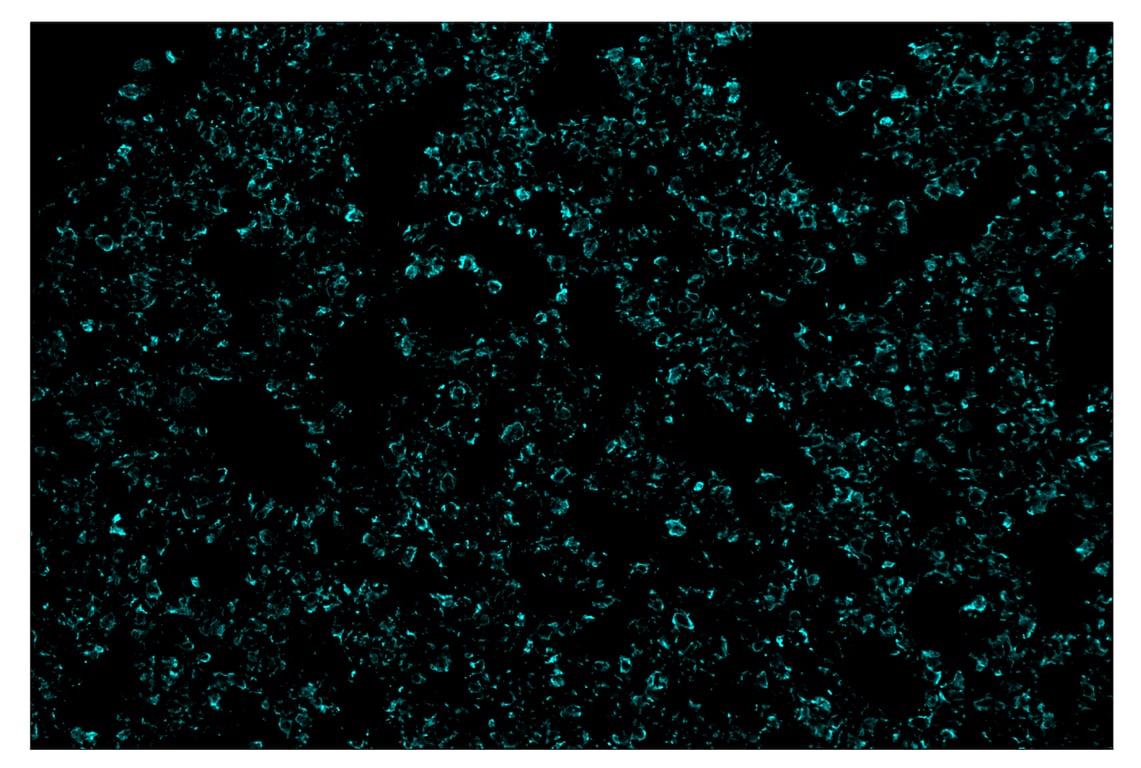

Pan-Keratin (Type I) (E6S1S) & CO-0072-647 SignalStar™ Oligo-Antibody Pair

| Pan-Keratin (Type I) (E6S1S) Rabbit mAb (SignalStar™ Conjugate 0072) | 74839 | 50 µl | H M | Rabbit IgG |

| Complementary Oligo (CO-0072-647) | 49132 | 22 µl |

SignalStar Oligo-Antibody Pairs are compatible with the SignalStar Multiplex IHC Buffer Kits for use in fluorescent multiplex imaging experiments. This product includes the oligo-conjugated antibodies and complementary oligos required for labeling your target protein on up to 10 slides. SignalStar Multiplex IHC Buffer Kits are required to amplify and image the target signal. Multiple oligo-antibody pairs can be conveniently combined into a multiplex panel using the SignalStar Multiplex IHC Panel Builder. SignalStar Multiplex IHC Kits & Reagents are not compatible with all of Cell Signaling Technology® products and protocols that are recommended for use in immunohistochemical assays.

Specificity/Sensitivity

Dysregulation/mutations in keratin genes can lead to a variety of disorders affecting the skin, hair, nails, and other epithelial tissues (3). While expression of keratins can be variable, immunohistochemical staining of keratins is widely used to help in the identification and classification of epithelial tumors, and may also provide prognostic information.

Keratins 8 and 18 (K8/K18) are expressed in simple epithelia of normal tissue, as well as in adenocarcinomas of the breast, lung, ovary, and gastrointestinal tract. Keratin 17 is expressed in basal keratinocytes of stratified epithelia, hair follicles, and sebaceous glands. Onset of keratin 17 expression coincides with the definition of major epithelial lineages during skin development (4). Keratin 14 (K14) is expressed in basal cells of stratified epithelia, and in basal-like subtypes of breast cancer and squamous cell carcinomas. Keratin 19 (K19) is expressed in glandular epithelia, including the liver, gallbladder, and pancreas, as well as in adenocarcinomas of the breast, thyroid, and bile duct. Keratin 20 (K20) is expressed in gastrointestinal epithelium, urothelium, and Merkel cells in the skin, as well as in colorectal carcinomas and some urothelial carcinomas. Keratin 5/6 (K5/6) is expressed in basal cells of stratified epithelia, including the skin, prostate, and breast, as well as in basal-like breast cancers, squamous cell carcinomas, and some lung carcinomas. Keratin 7 (K7) is expressed in glandular epithelia, such as those in the lung, breast, and female reproductive tract, as well as in adenocarcinomas of the lung, breast, and ovary (5,6).

Keratins, particularly K8, K18, and K19, serve as biomarkers for identification of circulating tumor cells (CTCs) (5).

Post-translational modifications, including phosphorylation, acetylation, ubiquitylation, sumoylation, glycosylation, and transamidation, have been shown to affect the functions of keratins in normal and disease states (6). Understanding the molecular mechanisms underlying these PTMs may provide insights into cancer pathogenesis.